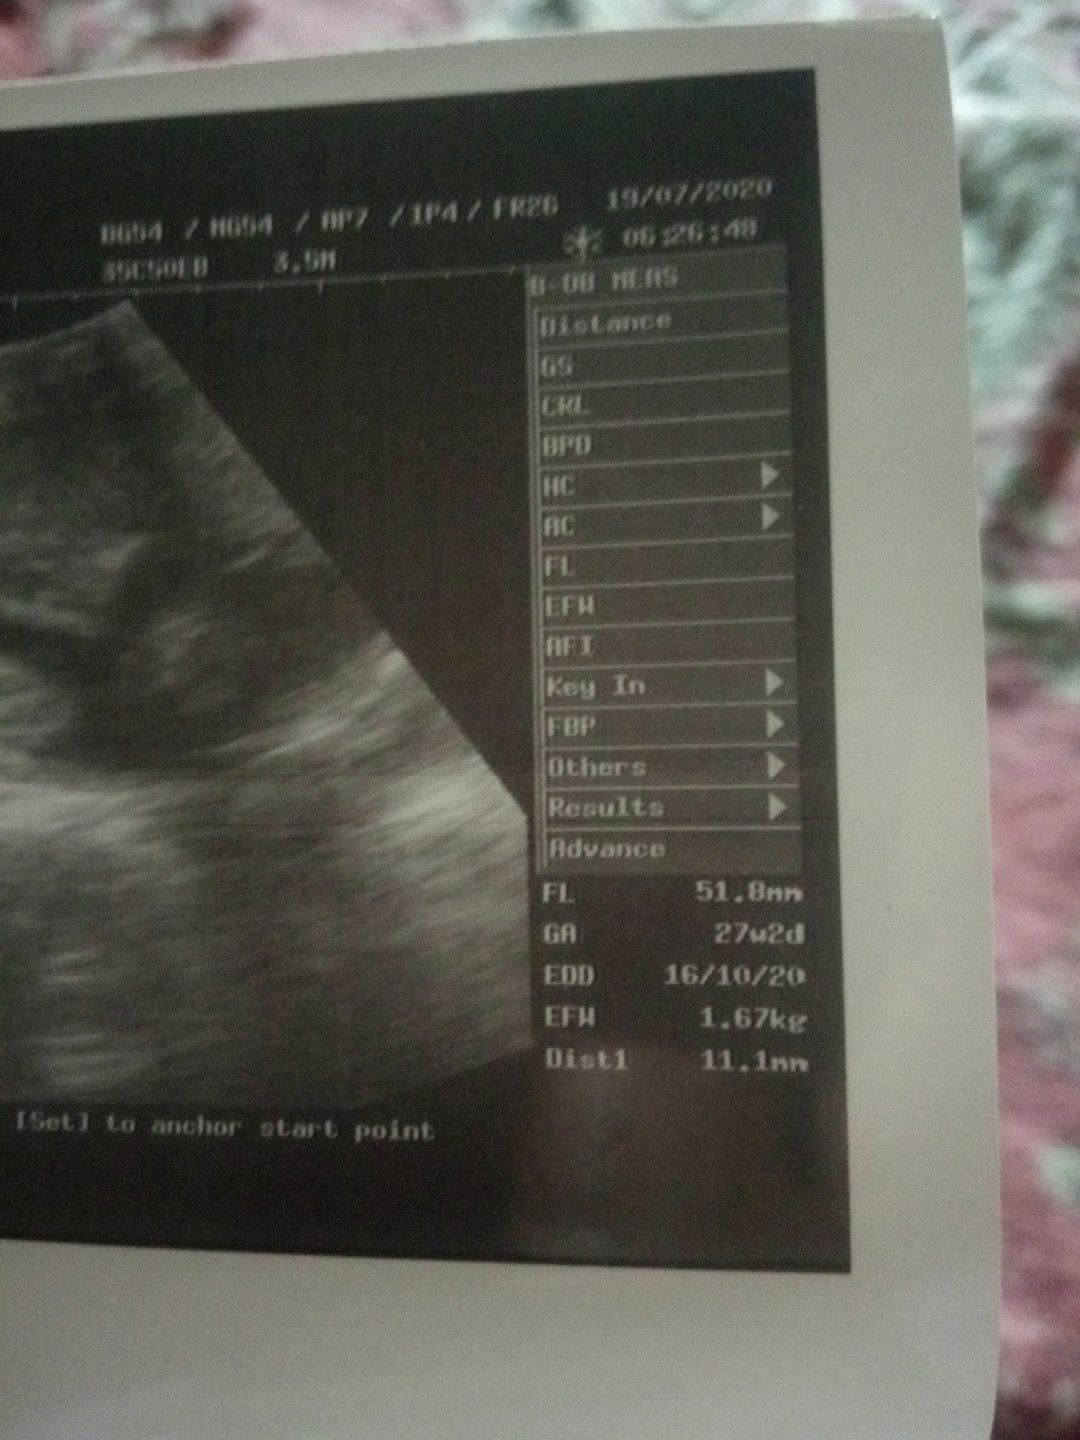

bbj

Bun hamil uk 26-27 Minggu bbj 1,67kg itu kebesaran gak? Tadi USG gk sempet tanya soalnya dokternya kayak buru² gitu..